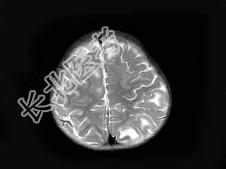

- 单项选择题男,1岁, 癫痫发作3次,智力反应低下, 头颅MRI扫描如图,最可能的诊断为 ( )

D、结节性硬化